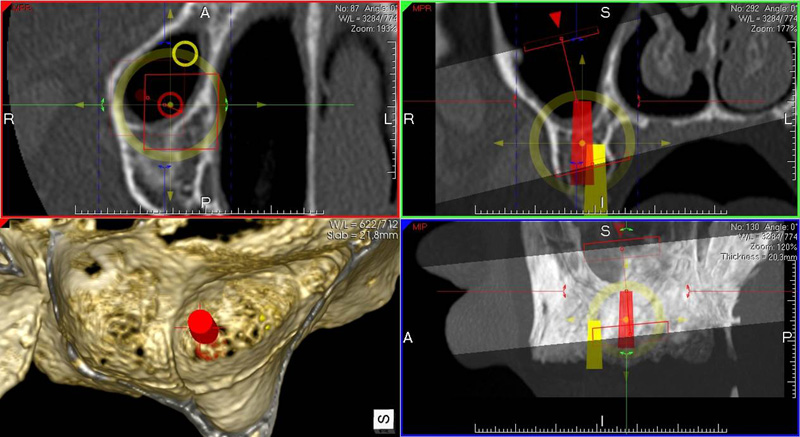

coDiagnostiX – Dental Wings

Jedná se o externí plánovací program, spojený se zubní laboratoří a frézovacím centrem, který využívá dat získaných z 3D rentgenu čelisti, otisku zubů a dásně (scanu zubů a dásně) a finálního návrhu protetické náhrady.

Tento program umožňuje tříprostorovou počítačovou simulaci při plánování pozic implantátů. Součástí programu je i databáze, ve které mohou být uloženy všechny typy implantátů od všech výrobců, včetně jejich délek, průměrů i tvarů.

Lékař si vytvoří všechny typy zobrazení potřebných pro naplánování – tedy 2D snímky (panoramatický), příčné řezy i 3D model.

Vidí zde i důležité anatomické útvary – čelistní dutinu, průběh nervu atd. Po proměření množství kosti – šířky i výšky vybere z databáze vhodný typ implantátu a umístí ho do požadované lokality. Ihned vidí jeho pozici ve všech 3 rovinách a na

všech snímcích i 3D modelu. Může upravovat podle potřeby jeho pozici, sklon atd.

Všechny vybrané a správně umístěné simulované implantáty se ukládají do „počítačové karty“ pacienta s jejich pozicí, délkou, průměrem, typem i sklonem. V programu také lékař navrhuje chirurgické šablony pro řízenou nebo navigovanou implantaci.

Lékař i pacient tedy ještě před vlastní operací vidí, jak by mělo ošetření probíhat a vypadat.